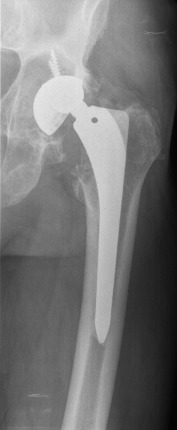

Fig. 2

Fig. 2.

Postoperative radiograph after first revision. A Bioball 4XL was required.

In September 2011 (ten years after primary THA), the patient came to our clinic complaining of hip pain. An important cup asymmetry that indicated wearing of the polyethylene was observed in the radiographic study (Fig. 1 ). The patient was 185 cm tall and weighed 110 kg (body mass index [BMI], 32.14 kg/m2 ). The patient underwent revision of the acetabular component and an exchange of the polyethylene component. Significant metallosis and loosening of the acetabular component was observed. The selected components for the revision were a 58 mm Trilogy® (Zimmer, Winterthur, Switzerland) acetabular shell attached with three (20, 30 and 35 mm) screws with a Trilogy® 58/36 cup. The Bicontact® stem was stable, thus no femoral stem revision was performed. This stem system was an uncemented titanium coated stem with a metaphyseal support. A correct fixation without any sign of collapse and anteversion were evaluated previously to the decision of maintaining the component. A Bioball® (Merete Medical, Berlín, Germany) with a 4XL neck was required to maintain the correct stability of the prosthesis due to laxity with pivoting and external rotation. The Bioball® system consists of different modular neck adapters which allow the surgeon to correct the length and offset of the neck when required. There are eight different sizes between “S” and “5XL” in ascending order, depending on the gap to correct. This implant could be useful specially in those revisions of either stem or acetabular component. Regarding to the case, the most probable cause of this laxity is the placement of the revision cup which is in a high, neutral and horizontal position (Fig. 2 ). The patient had a normal and uneventful postoperative period and remained asymptomatic for two years. He had a Merlé d’Aubigné Postel of 6.6.6 and a Harris Score of 94/100 at the last control.